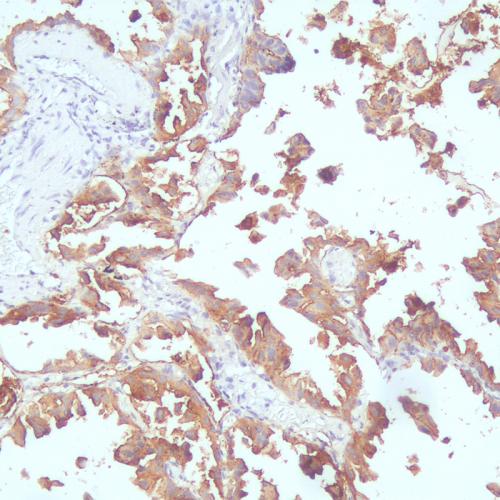

病理HE染色液主要用于顯示各種組織正常成分和病變的一般形態(tài)結(jié)構(gòu),進(jìn)行全面觀察。HE染色技術(shù)是病理解剖學(xué)、組織胚胎學(xué)、法醫(yī)學(xué)和生物學(xué)等領(lǐng)域最基本的技術(shù)操作,其在病理診斷、教學(xué)以及科研中廣泛應(yīng)用,具有重要價值。細(xì)胞中細(xì)胞核是由酸性物質(zhì)組成,它與堿性染料(蘇木素)的親和力較強(qiáng)。而細(xì)胞漿則相反,它含有堿性物質(zhì),與酸性物質(zhì)(伊紅)的親和力較大。因此,細(xì)胞或組織切片經(jīng)HE染色液染色后,細(xì)胞核被染成藍(lán)色,細(xì)胞漿、紅細(xì)胞、肌肉、結(jié)締組織、嗜伊紅顆粒等被染成不同程度的紅色或粉紅色,與藍(lán)色的細(xì)胞核形成鮮明的對比。